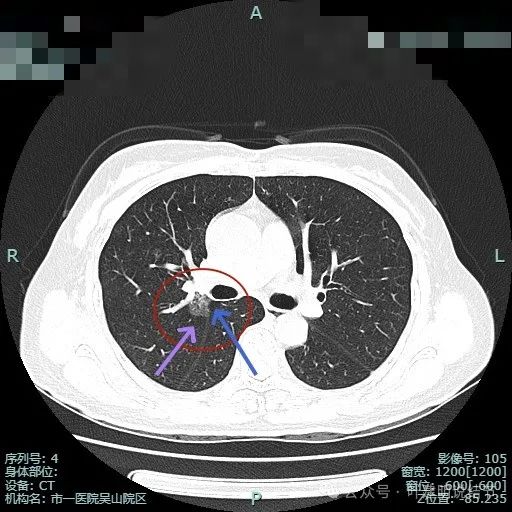

上叶前段有新的病灶出现(病灶3),也是磨玻璃密度,轮廓与边界清,有空泡征;病灶2密度不纯,轮廓较清,与斜裂没有间隙。

病灶2密度较淡,病灶3其实也不太纯的。

病灶2边缘部分的样子;病灶3有血管贴边,表面不光滑,有微小血管进入。胸膜下另有一微小淡磨玻璃结节,考虑也是肿瘤范畴的,大概是肺泡上皮增生之类(病灶4)。

病灶2几乎不见了;病灶3有血管进入,表面浅分叶,整体轮廓与边界清。

病灶3血管贴边走行。